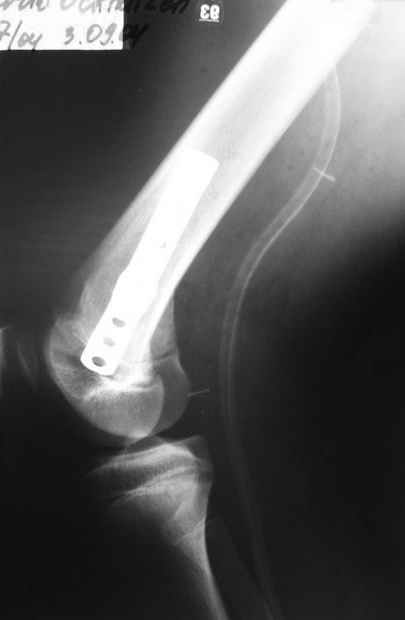

Как вариант решения прогрессирующей вальгусной деформации коленного сустава я бы предложил косую остеотомию дистального отдела бедра с фиксацией пластиной и компрессирующим винтом.

Взгляните на снимки , может быть это вам поможет.

Около 5 лет применяю этот тип дистальной остеотомии бедра для коррекции механической оси Н/К ( более 20 случаев) - достаточно эффективная операция.

Сравни состояние артикулирующих поверхностей в представленном тобой примере и обсуждаемом случае.